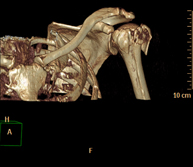

- Osteoarticular- TC Hombro Exploración radiológica que mediante un sistema de rayos X y detectores que giran alrededor del paciente, reconstruyendo las imágenes por ordenador (TC Multidetector), permite el estudio de huesos, músculos y articulaciones del hombro. Exploración radiológica que mediante un sistema de rayos X y detectores que giran alrededor del paciente, reconstruyendo las imágenes por ordenador (TC Multidetector), permite el estudio de huesos, músculos y articulaciones del hombro.

- TC Caderas Exploración radiológica que mediante un sistema de rayos X y detectores que giran alrededor del paciente, reconstruyendo las imágenes por ordenador (TC Multidetector), permite el estudio de huesos, músculos y articulaciones de la cadera. Exploración radiológica que mediante un sistema de rayos X y detectores que giran alrededor del paciente, reconstruyendo las imágenes por ordenador (TC Multidetector), permite el estudio de huesos, músculos y articulaciones de la cadera.